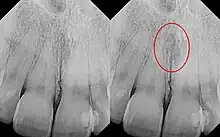

| Identical images with heart-shaped radiolucency highlighted in right film. | |

The nasopalatine duct cyst (NPDC) occurs in the median of the palate, usually anterior to first molars. It often appears between the roots of the maxillary central incisors. Radiographically, it may often appear as a heart-shaped radiolucency. It is usually asymptomatic, but may sometimes produce an elevation in the anterior portion of the palate. It was first described by Meyer in 1914.[1]

As a cyst, the nasopalatine duct cyst requires histological analysis for a definitive diagnosis. Radiographically, the nasopalatine cyst appears as a well-demarcated round, ovoid, or heart-shaped structure presenting in the midline of the maxilla.[6]